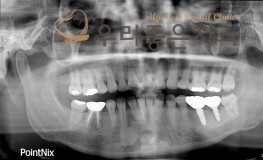

임플란트